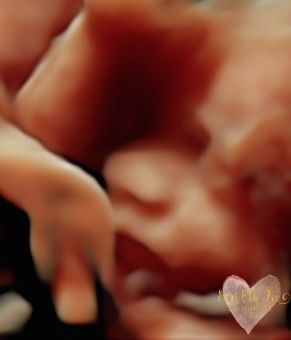

3D/4D/5D Ultrasound Gallery

Take a peek at our Photo Gallery. All of our 2D, 3D, 4D, HD elective ultrasound images are truly ours. They come directly off our machine from our highly trained staff. We can start getting great 3D/4D images as early as 10 weeks!